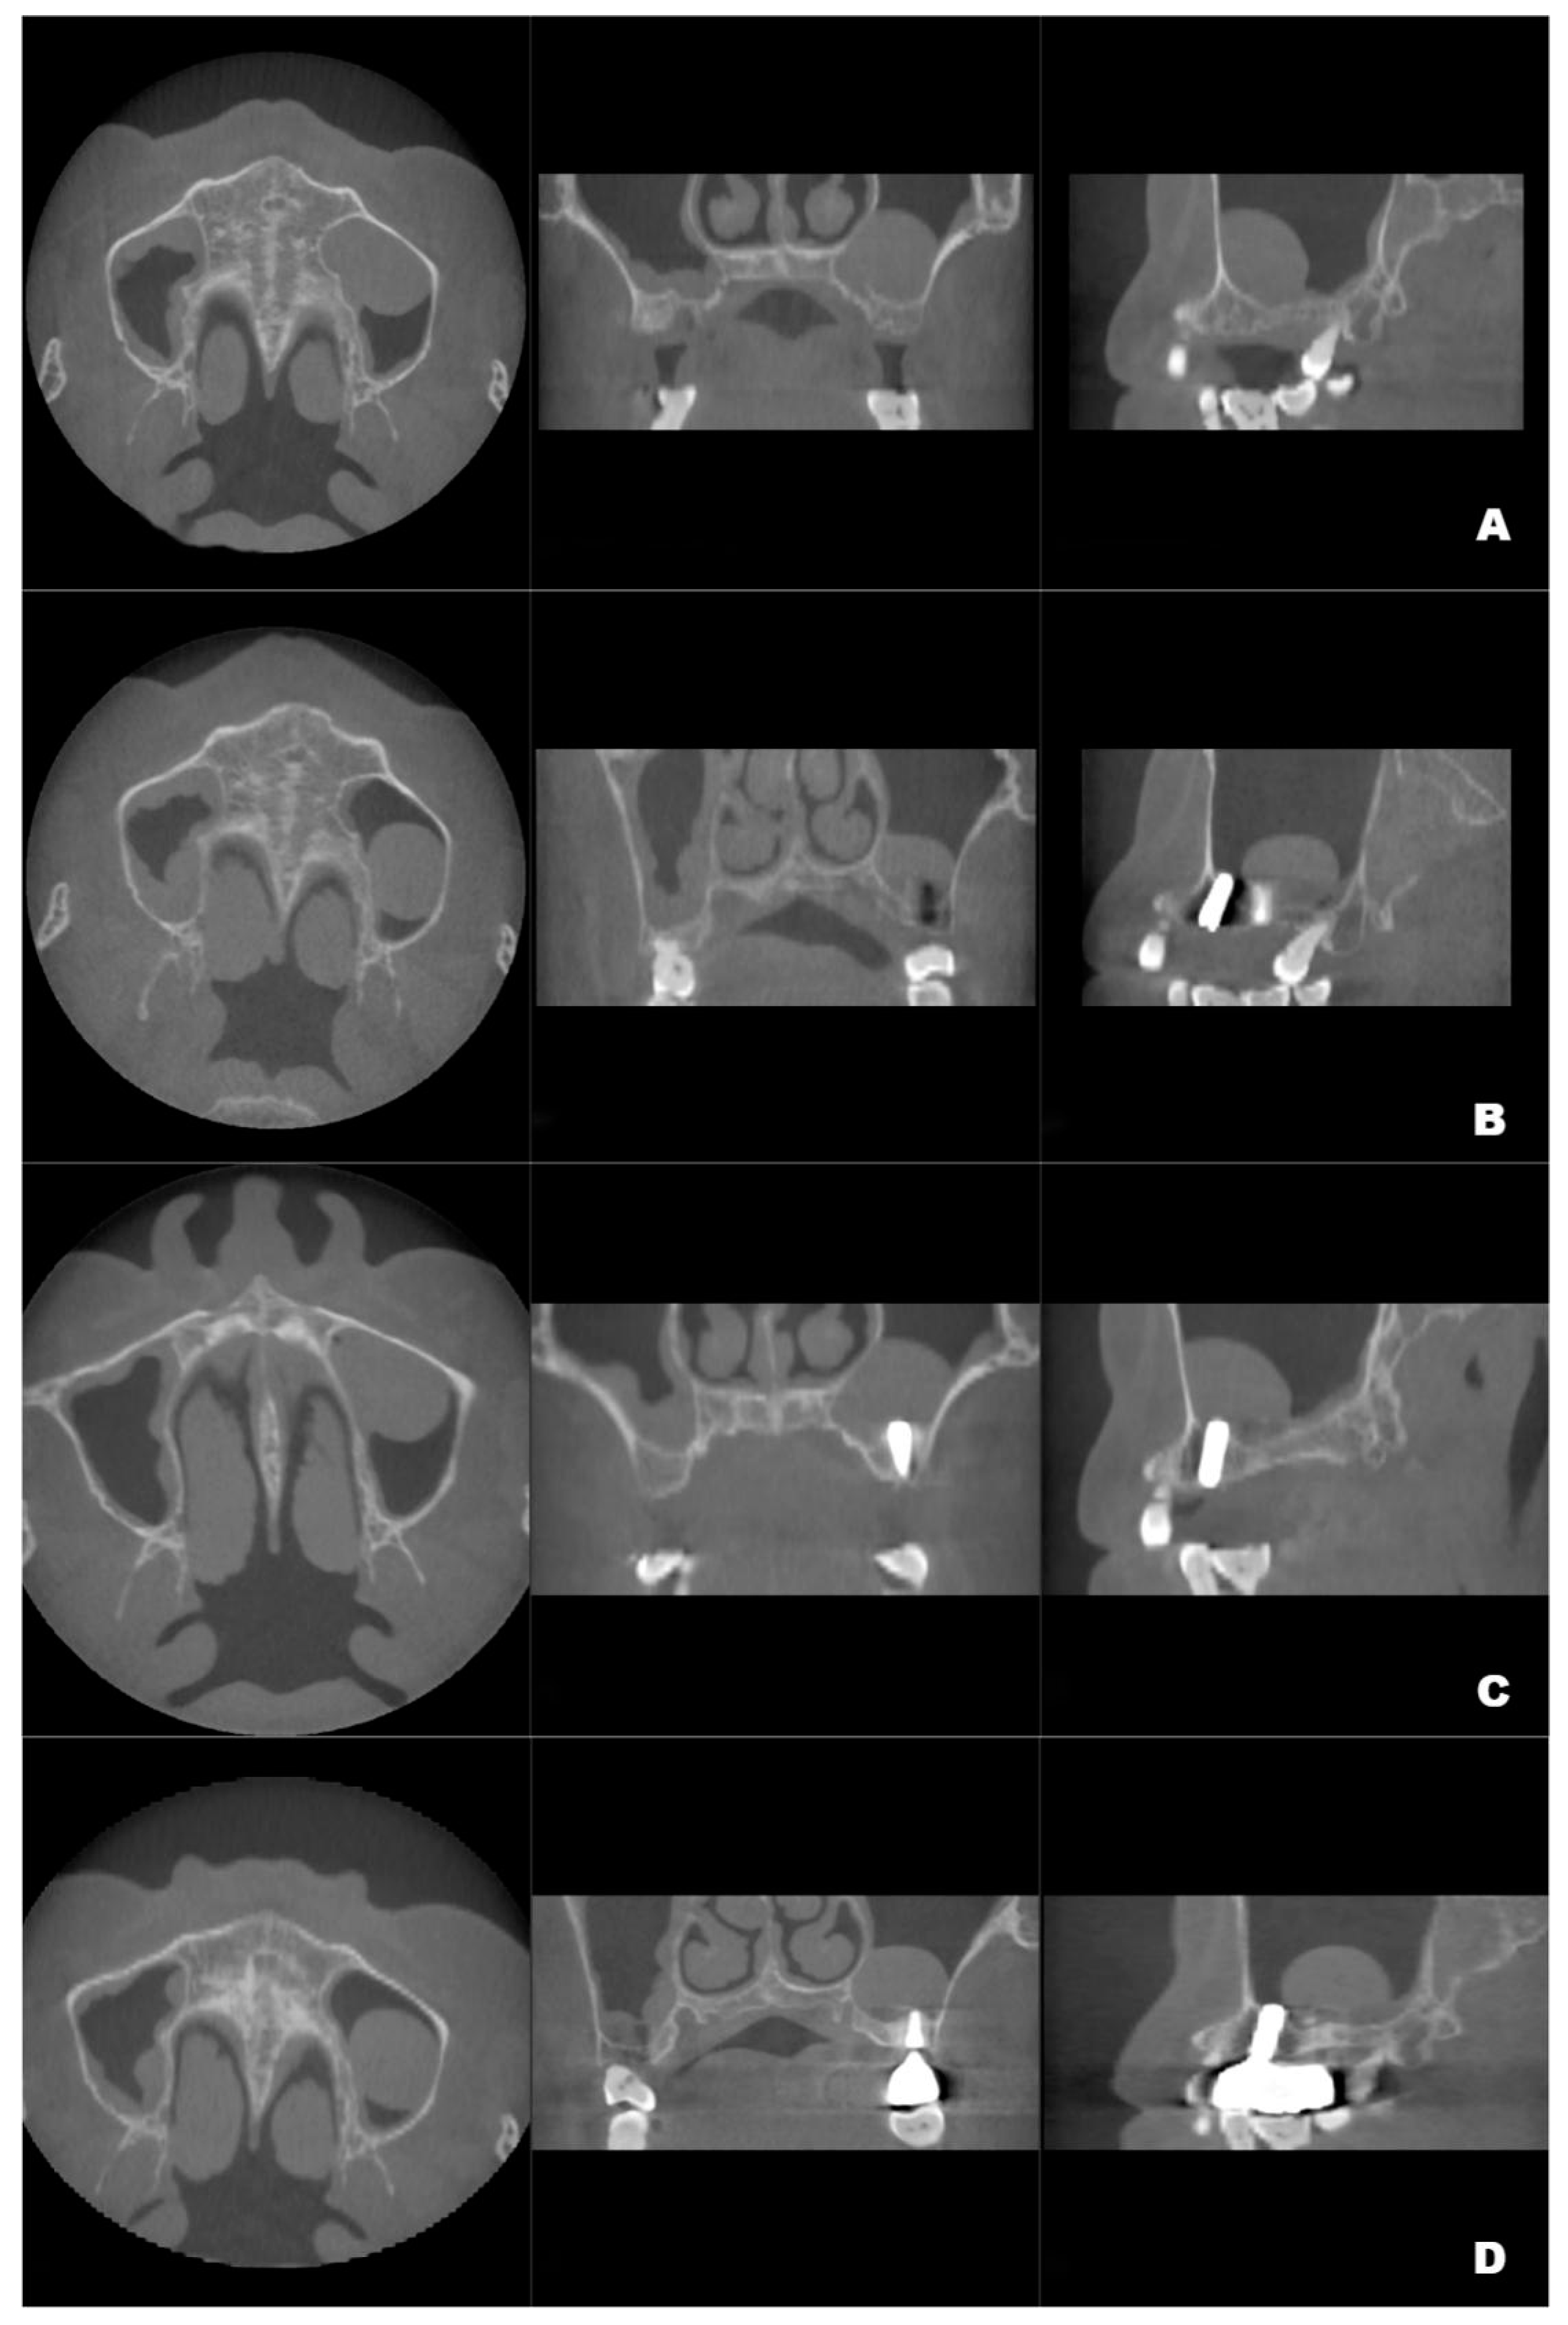

Figure 1.

Preoperative CBCT showing the crestal height of L1 = 8.688 mm, (A), and local alveolar ridge width of W1 = 8.688 mm, (B), of the residual bone of the left maxillary second premolar and the crestal height of L2 = 4.285 mm, (C), and alveolar ridge width of W2 = 10.130 mm, (D), of the residual bone of the left maxillary first molar.

CBCT examinations were performed on CBCT scanners (3D Accuitomo, J. Morita Mfg. Corp., Kyoto, Japan) using the following parameters: 85-kV tube voltage, 5.0-mA tube current, field of view of 100 mm × 50 mm, and slice thickness of 1.0 mm. Dental CBCT scans showed that the local alveolar ridge width was optimal (8.688 mm for the left maxillary second premolar and 10.130 mm for the first molar) (Figure 1B,D); however, sinus augmentation was needed because the height of the residual alveolar bone in the posterior maxillary area was insufficient for implant placement. The patient was observed to have type 3 bone quality in the posterior maxilla on both sides, and according to our observation, there was no obvious thickening of the nasal mucosa in the pre-operative CBCT image. Notably, the height of the crestal bone between the sinus floor and the alveolar ridges of the left maxillary second premolar and first molar were 8.688 mm and 4.385 mm, respectively (Figure 1A,C). CBCT also revealed a homogeneously opaque, dome-shaped, and well-delineated lesion (volume, 3.795 mm3) in the left maxillary sinus (Figure 1 and Figure 2A); the lesion did not exhibit an epithelial lining. Prior to attending our clinic, the patient had consulted an otolaryngologist and received confirmation that no mucous cyst was present (no aggressive lesion appearance, significant bone resorption, or invasion of adjacent structures observed on radiologic imaging). Because the patient did not exhibit relevant symptoms, the otolaryngologist suggested conservative management of the pseudocyst. Accordingly, the treatment plan comprised osteotome sinus floor elevation, with simultaneous implant placement on the left side, in the presence of an antral pseudocyst.